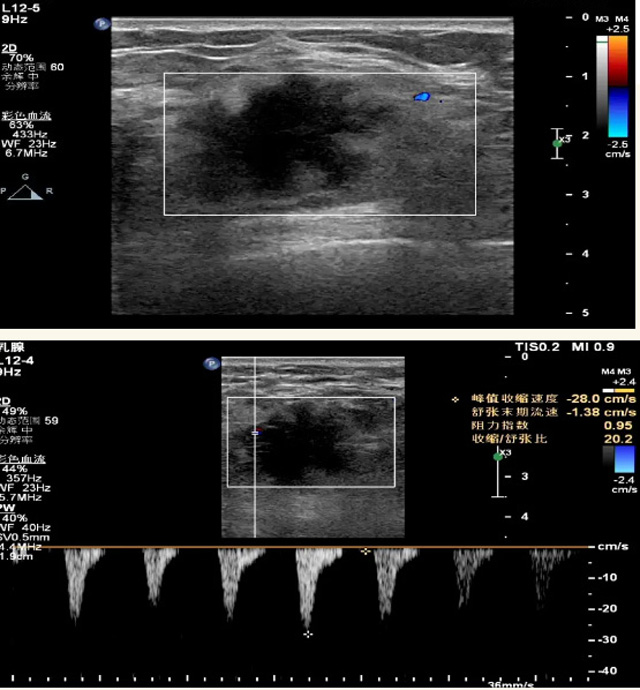

乳腺B超檢查無輻射,對(duì)囊性病變敏感,可以實(shí)時(shí)觀察病灶。超聲引導(dǎo)活檢跟手術(shù)前的定位。就是它對(duì)于微小的鈣化查出率比鉬靶稍微差點(diǎn)。磁共振MRI檢查也是是沒有輻射的,對(duì)備孕跟已經(jīng)懷孕的人士比較友好。不用擔(dān)心這個(gè)輻射影響胎兒?jiǎn)栴}。對(duì)乳腺病灶敏感性較高,致密乳腺病灶、乳腺癌的復(fù)發(fā),準(zhǔn)確鑒別囊性及實(shí)性病變??梢詭椭R床醫(yī)生判斷惡性、良性病變。但是MRI磁共振對(duì)微小鈣化不明顯,微鈣化還是鉬靶靠譜點(diǎn)。檢查時(shí)間比較長(zhǎng),有偽影的影響。費(fèi)用相對(duì)B超,鉬靶高很多。

乳腺B超